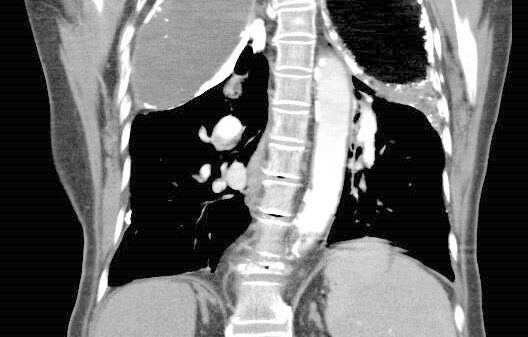

07 IV Paraffin Plombage/Oleothorax and Acute Pleural Empyema